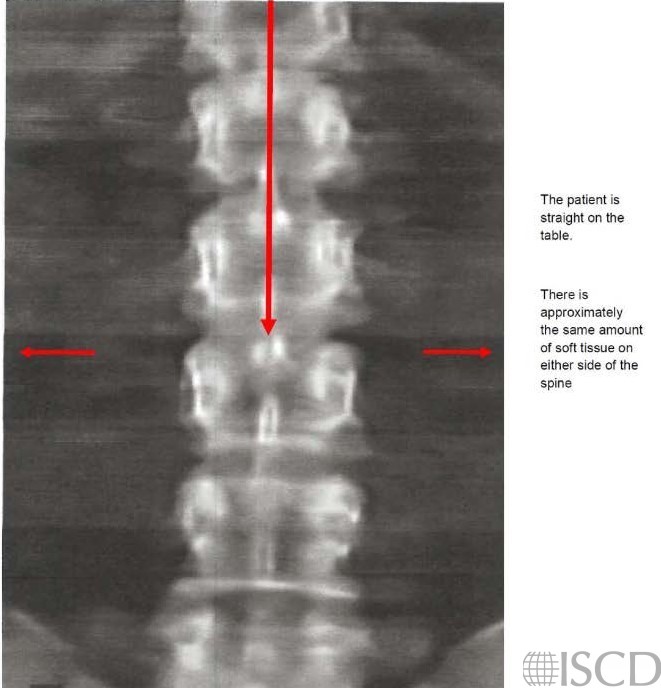

Normal Hologic Spine Scan

This image shows a normal Hologic spine scan.

The patient should be in the center of the table with approximately equal amounts of soft tissue on each side.

This is a normal Hologic spine scan.

The spine is straight on the table and is parallel to the sides of the image. The spine is centered in the scan field, with roughly equal amounts of soft tissue on both sides. This won’t always be possible, especially with individuals with degenerative changes in their spine.